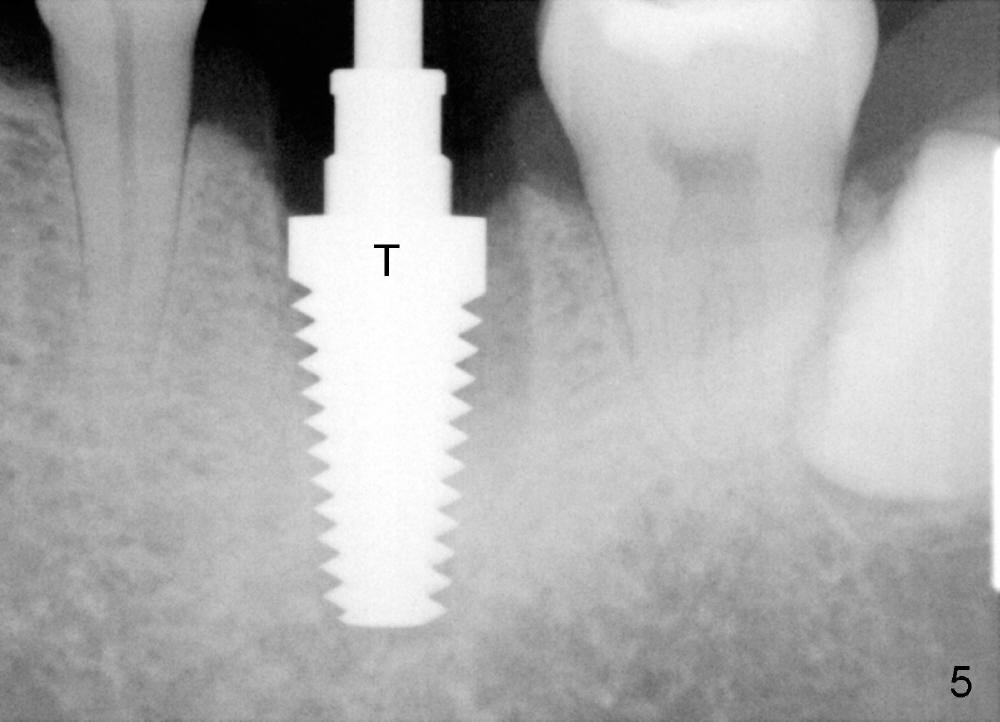

A 41-year-old man has discomfort in the lower left 1st molar. Exam shows swelling and a fistula in the mesiobuccal gingiva (Fig.1 >) and large radiolucency around the mesial root (Fig.2 *). After extraction and thorough debridement, osteotomy is initiated in the mesial socket, but the upper portion of the reamer (Fig.3 R, 2.5 mm) is placed in the middle of the edentulous space. By the time 5 mm reamer is removed, the osteotomy (Fig.4 O) forms mainly in the mesial socket with the septum (S) deviated to the distal socket. A 7x17 mm tap is placed with stability (Fig.5 T). An implant with the same dimension is placed with insertion torque more than 60 Ncm (Fig.6 I). With the large implant, two proximal sutures are able to close the remaining socket gaps (Fig.7). The swelling and fistula disappears and the gingiva tightly surrounds the implant in 1 week postop (Fig.8).